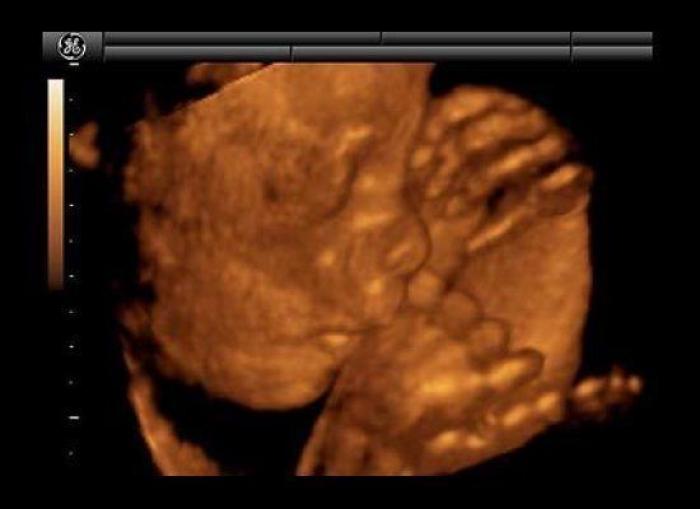

En esta galería puedes ver en fotos como es el desarrollo de un feto de semana en semana:

Desarrollo del feto, en fotos